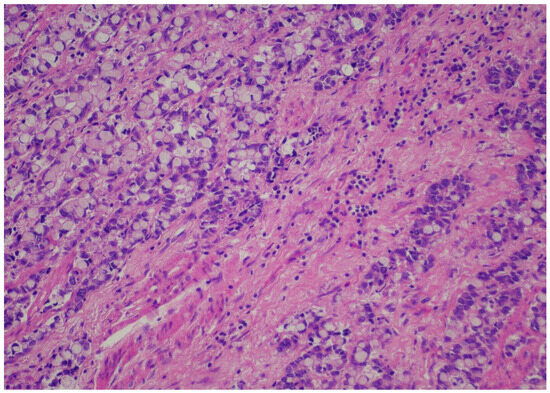

Records from patients with gastric or esophageal adenocarcinoma operated on in a single academic institution during the time period from January 2022 until January 2024 were reviewed after institutional review board permission. Demographics, including age and gender, were recorded for all patients. Only patients with adenocarcinomas who underwent esophagectomy or gastrectomy according to respective tumor location were included. Only patients who were operated on after the completion of the neoadjuvant FLOT regimen were included in the analysis. Type of operation performed and pathology reports/relevant pathology slides were reviewed, including total number of lymph nodes, positivity or negativity of lymph nodes, node positivity after regression, and node negativity with regression. Tumor regression (TRG) score was reported according to the Mandard classification [21]. TRG values ranged from 1–5, with 1 designating no residual cancer cells, TRG 2 residual cancer cells, TRG 3 fibrosis outgrowing residual cancer, TRG 4 residual cancer outgrowing fibrosis, and TRG 5 absence of regressive features. Staging was performed according to the American Joint Commission on Cancer (AJCC), 8th edition [22]. All relevant slides were also reviewed to calculate TIL scores for all patients, expressed as a numerical score, according to relevant guidelines from international consortia on tumor-infiltrating lymphocytes [23]. When no tumor could be identified after neoadjuvant treatment, by definition, no TIL scores could be assigned. More specifically, a review of the pathology slides measurement of TILs did not require any stains on the slides but rather only calculating TIL scores from “measuring” the number of lymphocytes relevant to the tumor. The reader is directed to the aforementioned reference for the exact protocol used to calculate TIL scores. Pathology reports for all relevant operations were reviewed, and pathology slides were re-reviewed by 2 independent expert pathologists (CG and DR) to calculate the TIL score. A TIL score from 0–80 was granted, and where no tumor was found, “no tumor” was designated for TIL score calculations. Figure 1 and Figure 2 depict slides from our patient cohort, with the first corresponding to a TIL-high patient, while the latter originates from a TIL-low patient.

The SPSS package [IBM SPSS statistics version 29.0.2.0(20)] was used for all statistical analyses. In order to create subgroups of TIL patients of sufficient sample size, we created two groups for TILs, namely TIL-low and TIL-high groups, with the TIL-low group containing scores from 0–30 and the TIL-high group containing numbers from 40–80. Representative pictures from pathologic slides from our patient series are provided in pictures 1 (TIL-low) and 2 (TIL-high). We affirmed that both TIL-low and TIL-high groups contained more than 25 patients each, and therefore, by definition, we assumed that the sample size followed a normal distribution and included categorical data; thus, Spearman’s r correlative statistic could be used for analysis. With regards to the Mandard score, we stratified patients into a “good response” TRG1 and TRG2 and a “bad response” TRG 3, TRG 4, and TRG 5. Correlation analysis between TRG and the TIL-low or TIL-high group was performed using the Spearman’s r statistic and Kendall’s tau statistics.

Figure 2. TIL-low patient.